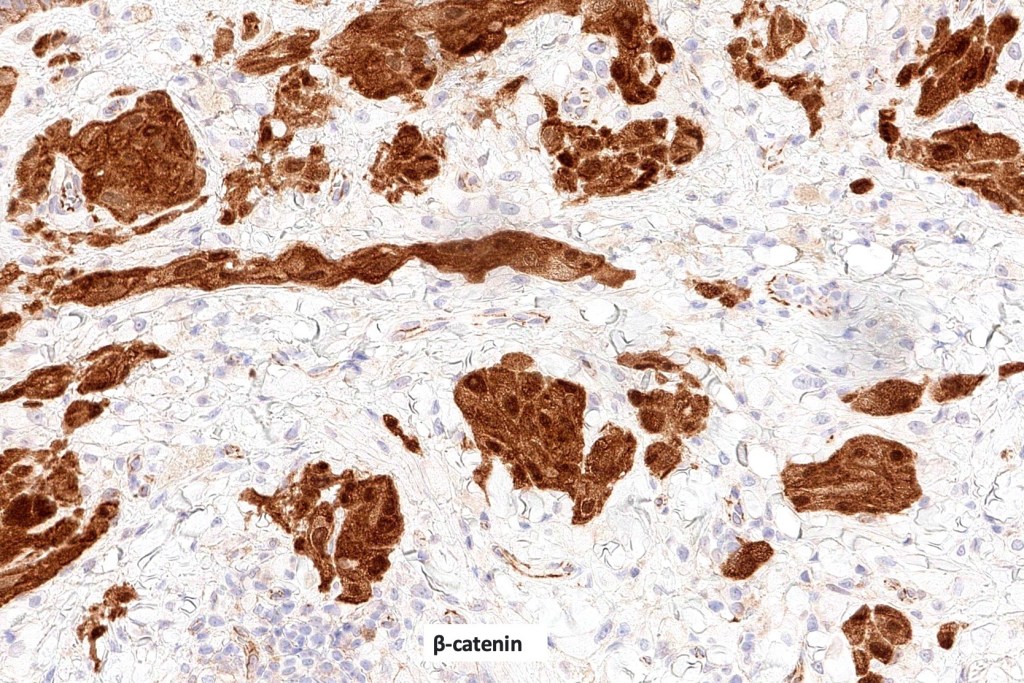

•Strong nuclear & cytoplasmic expression of β catenin, cyclin D1 & LEF1

•WNT pathway activated usually through gain of function mutations of CTNNB1